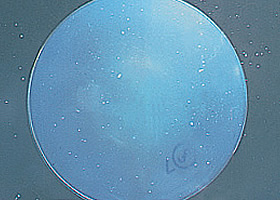

ダメージを受けた角膜内内皮細胞

正常な角膜内内皮細胞

角膜内皮細胞の死滅減少→角膜の混濁[水疱性角膜症]→視力低下

継続的に酸素不足が続くと、角膜の細胞が死んでしまい、一度失った細胞は再生されることはありません。

また残っている細胞も大きさや形にばらつきが出てしまいます。